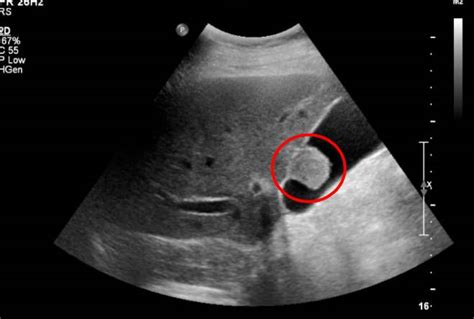

切除胆囊后,胆总管会出现代偿性扩张。如此功能丧失,将出现类似胆绞痛和不适感。切除人的胆囊后果表现为:①厌食脂肪性食物,由于没有浓缩的胆囊胆汁进入小肠,肠内的胆汁酸量达不到临界微胶粒浓度(见吸收),所以摄入较多脂肪时,将出现脂肪消化不良,从而引起厌食脂肪性食物;②胆汁酸池减少,胆汁酸的肠肝循环次数增加,结果肠内胆汁酸量下降不致过多;③胆汁内次级胆汁酸含量增多,这是由于切除胆囊后,初级胆汁酸进入肠腔的量增多,肠内细菌作用所产生的次级胆汁酸量也增多并被吸收再进入胆汁的缘故;④胆汁中胆固醇减少,胆固醇由饱和变成不饱和状态,这对于防止胆固醇结石再生成是有利的。

胆囊摘除对人体消化脂肪有一些影响,便影响不大,一般术后三到六个月就可以适应,有部分人没有不适感,胆囊切除术后肠道的肿瘤发生率可能要升高一些。如有必要,胆囊是可以切除的,因胆囊炎,胆囊结石可能引起胆源性胰腺炎,化脓性胆管炎,症状较重,后果也较重。医生询问: